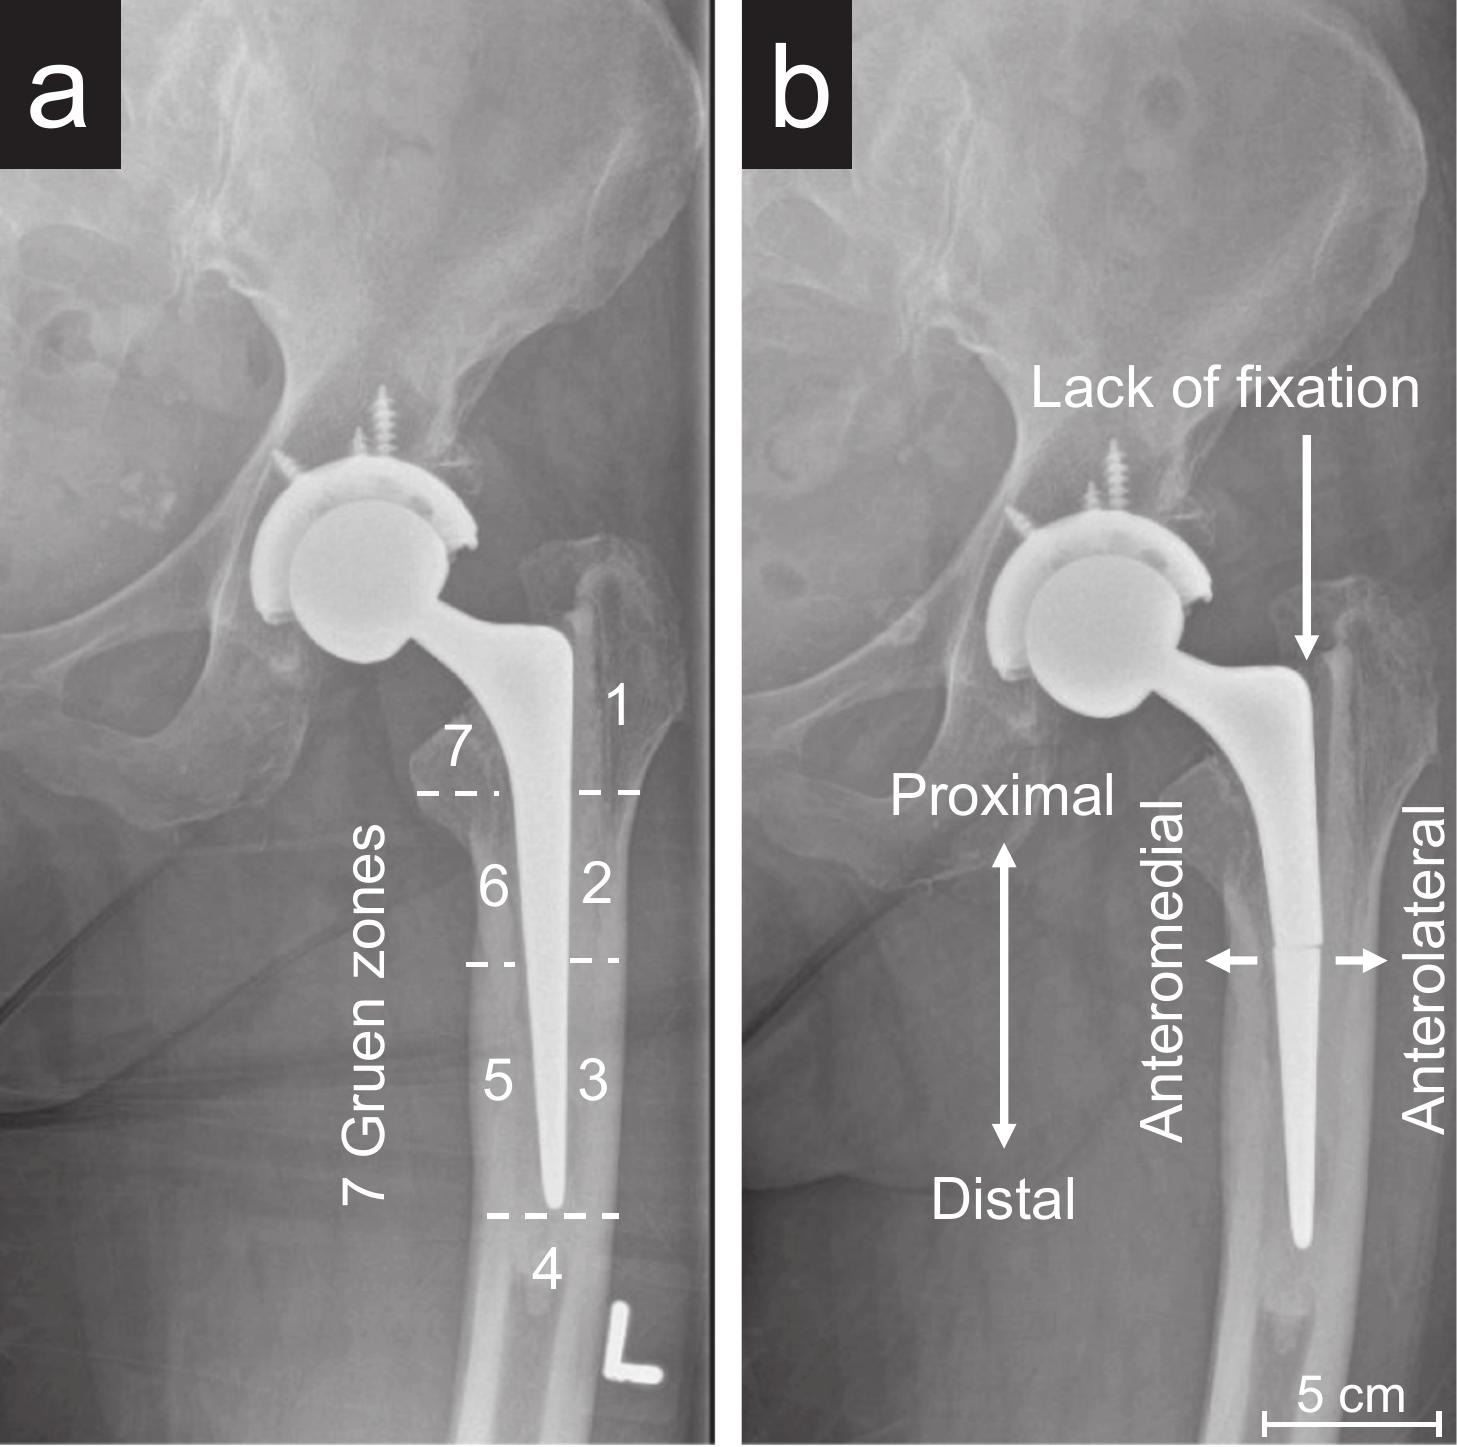

Hip replacements are widely regarded as one of the most successful medical procedures, restoring mobility and quality of life for millions. However, a small number of implants can fail over time, requiring revision surgery; understanding why could be crucial for improving outcomes for patients.

The research focused on the combined effects of mechanical stress and corrosion inside the body - together know as known as 'corrosion fatigue'. In addition to mechanical fatigue, the team found that corrosion played a significant role. The body’s internal environment can gradually degrade stainless steel, particularly in areas where stress is concentrated. Corrosion fatigue was identified as a major contributor to implant failure.

Importantly, the research revealed that microscopic surface damage can act as a starting point for cracks. Once initiated, these cracks may grow slowly and remain undetected until they reach a critical size, potentially leading to sudden failure of the implant.